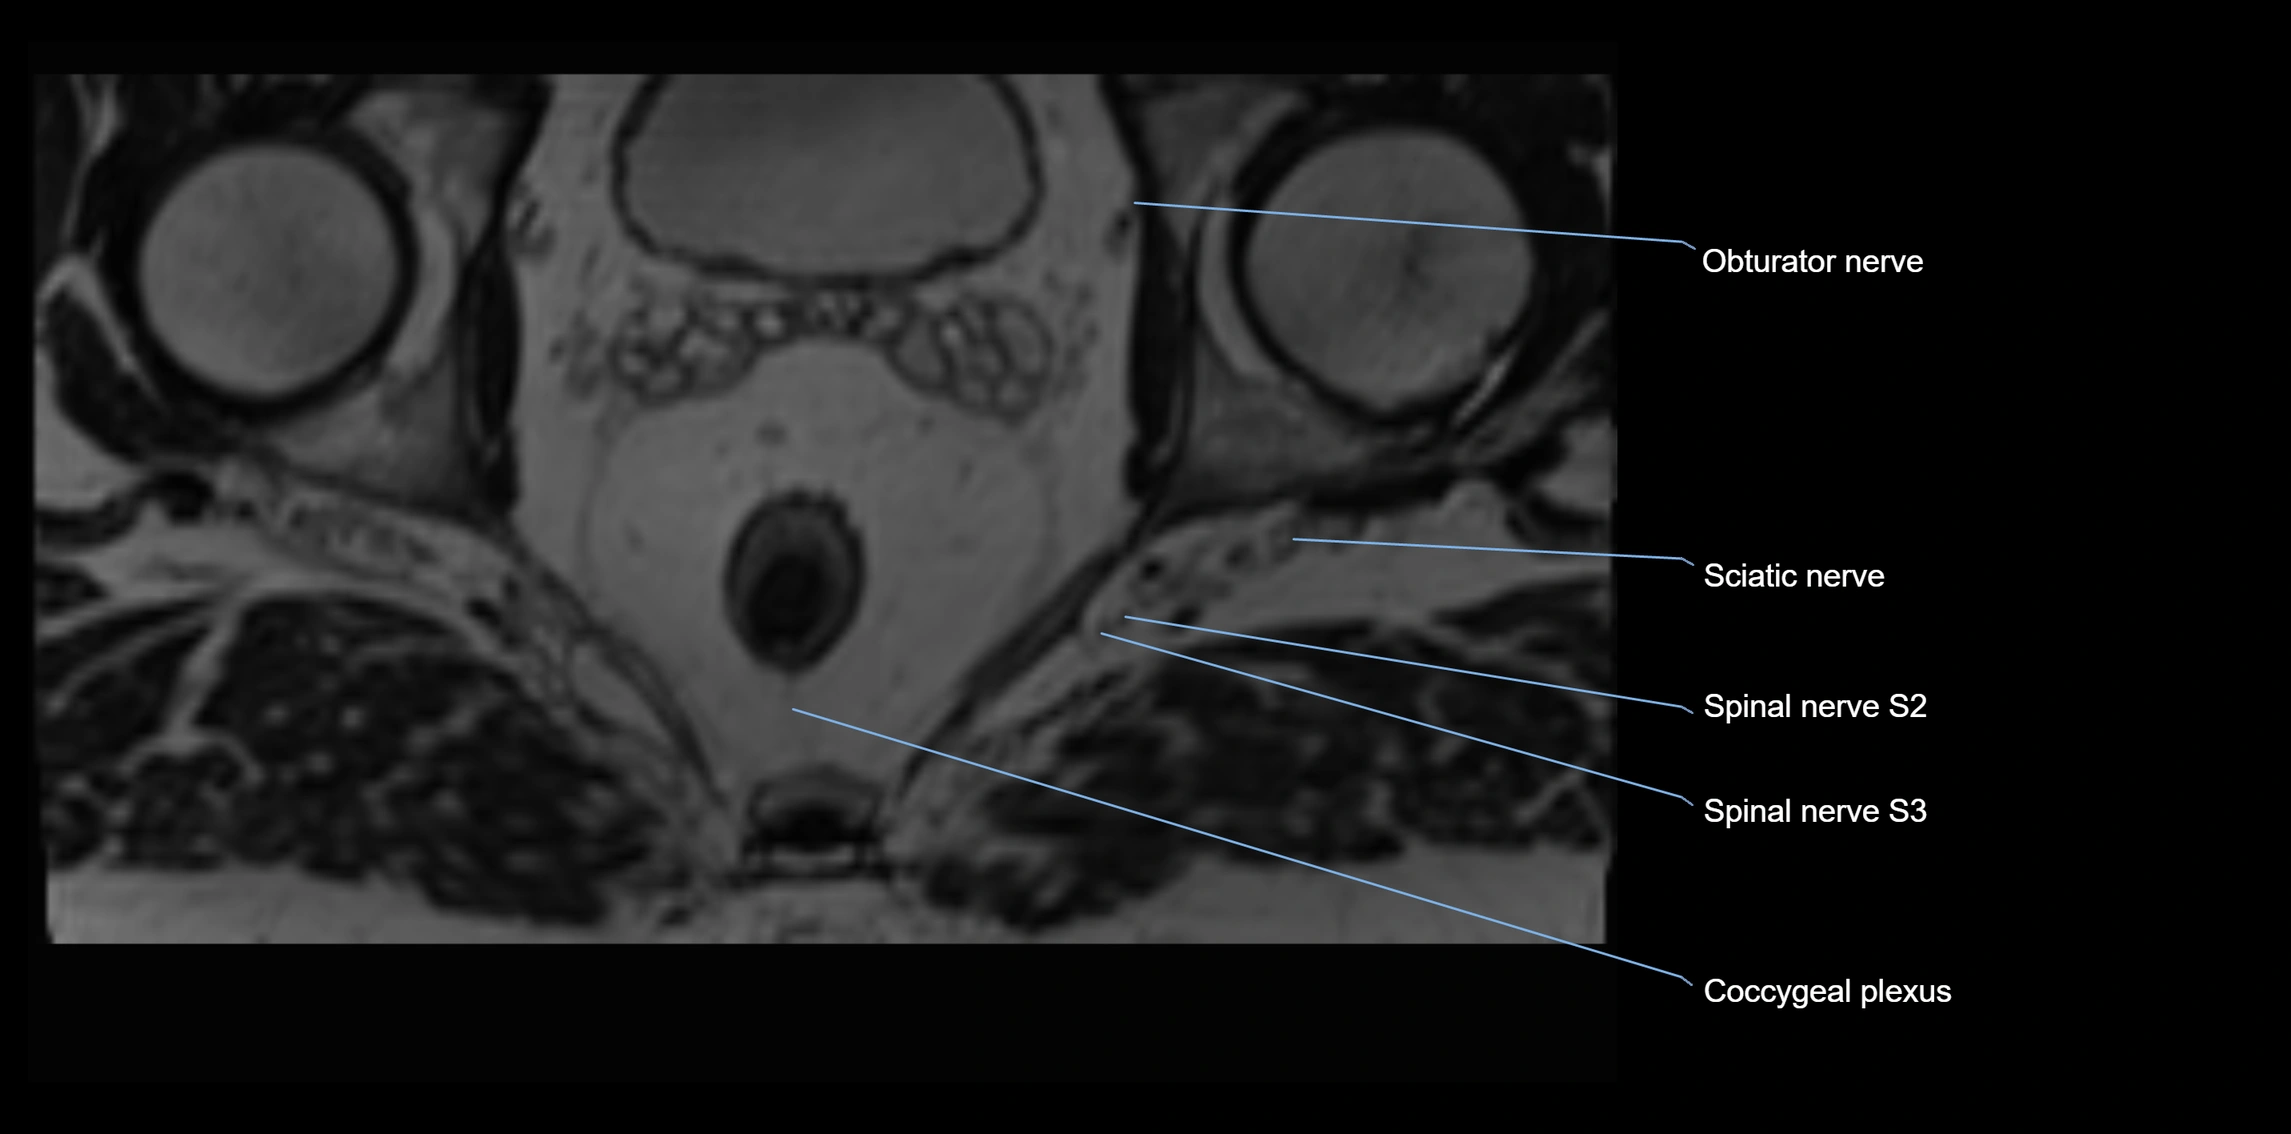

MRI Appearance

T1-weighted images:

• Nerve appears as a very thin low-to-intermediate signal intensity structure

• Surrounded by bright fat, aiding visualization

T2-weighted images:

• Nerve shows intermediate to mildly hyperintense signal compared to muscle

• Pathological involvement appears brighter

STIR (Short Tau Inversion Recovery):

• Normal nerve appears dark

• Inflamed or entrapped nerve appears bright hyperintense

T1 Fat-Sat Post-Contrast:

• Normal nerve enhances minimally

• Pathologic nerve (neuritis, entrapment, tumor infiltration) shows focal or diffuse enhancement

3D T2 SPACE / CISS:

• Nerve appears intermediate to mildly hyperintense compared to muscle

• Surrounded by bright fat or CSF, improving visualization

• Best sequence for mapping small pelvic nerves such as the anococcygeal

MRI image

image